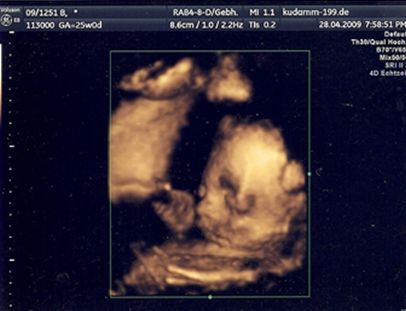

Unsere Kampfkruemeline! SSW 25+0!